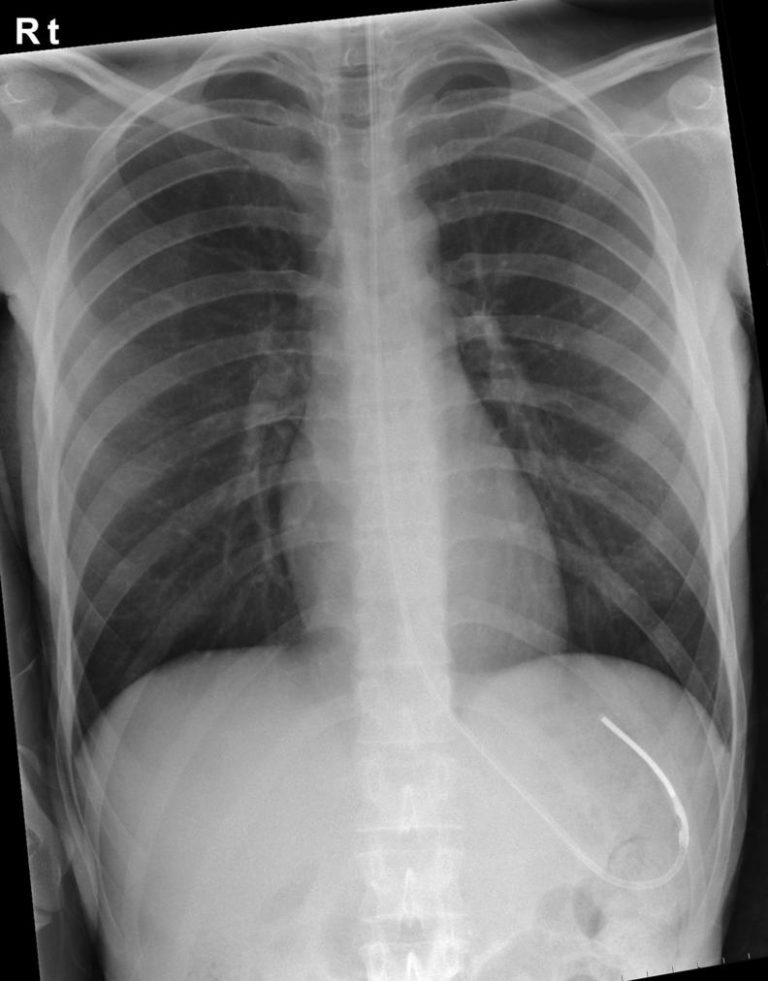

Nasogastric (NG) Tube Placement Oxford Medical Education Why Is There Blood In Ng Tube A nasogastric tube (ng tube) is a thin, flexible plastic tube that’s used for temporary. after three attempts, there was a large amount of bleeding through the tube and vital signs changed dramatically, with. traumatic injury to the gi mucosa may occur during ng tube insertion and can result in gi bleed, especially in. Ng lavage does not. Why Is There Blood In Ng Tube.